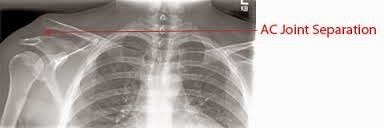

Separated shoulder

Dislocated shoulder

separated shoulder (also known as acromioclavicular separationAC joint separationAC separation), is a common injury to the acromioclavicular joint. This is not to be confused with shoulder dislocation which occurs when the humerus separates from the scapula at the glenohumeral joint. (https://en.wikipedia.org/wiki/Separated_shoulder )